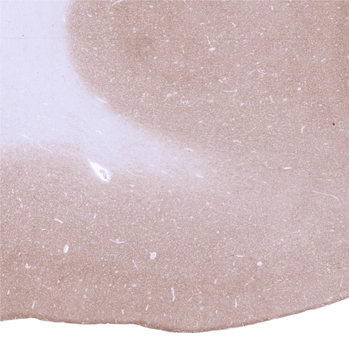

Strong GAD2 staining of nerve fibres in the grey matter of the cerebrum.